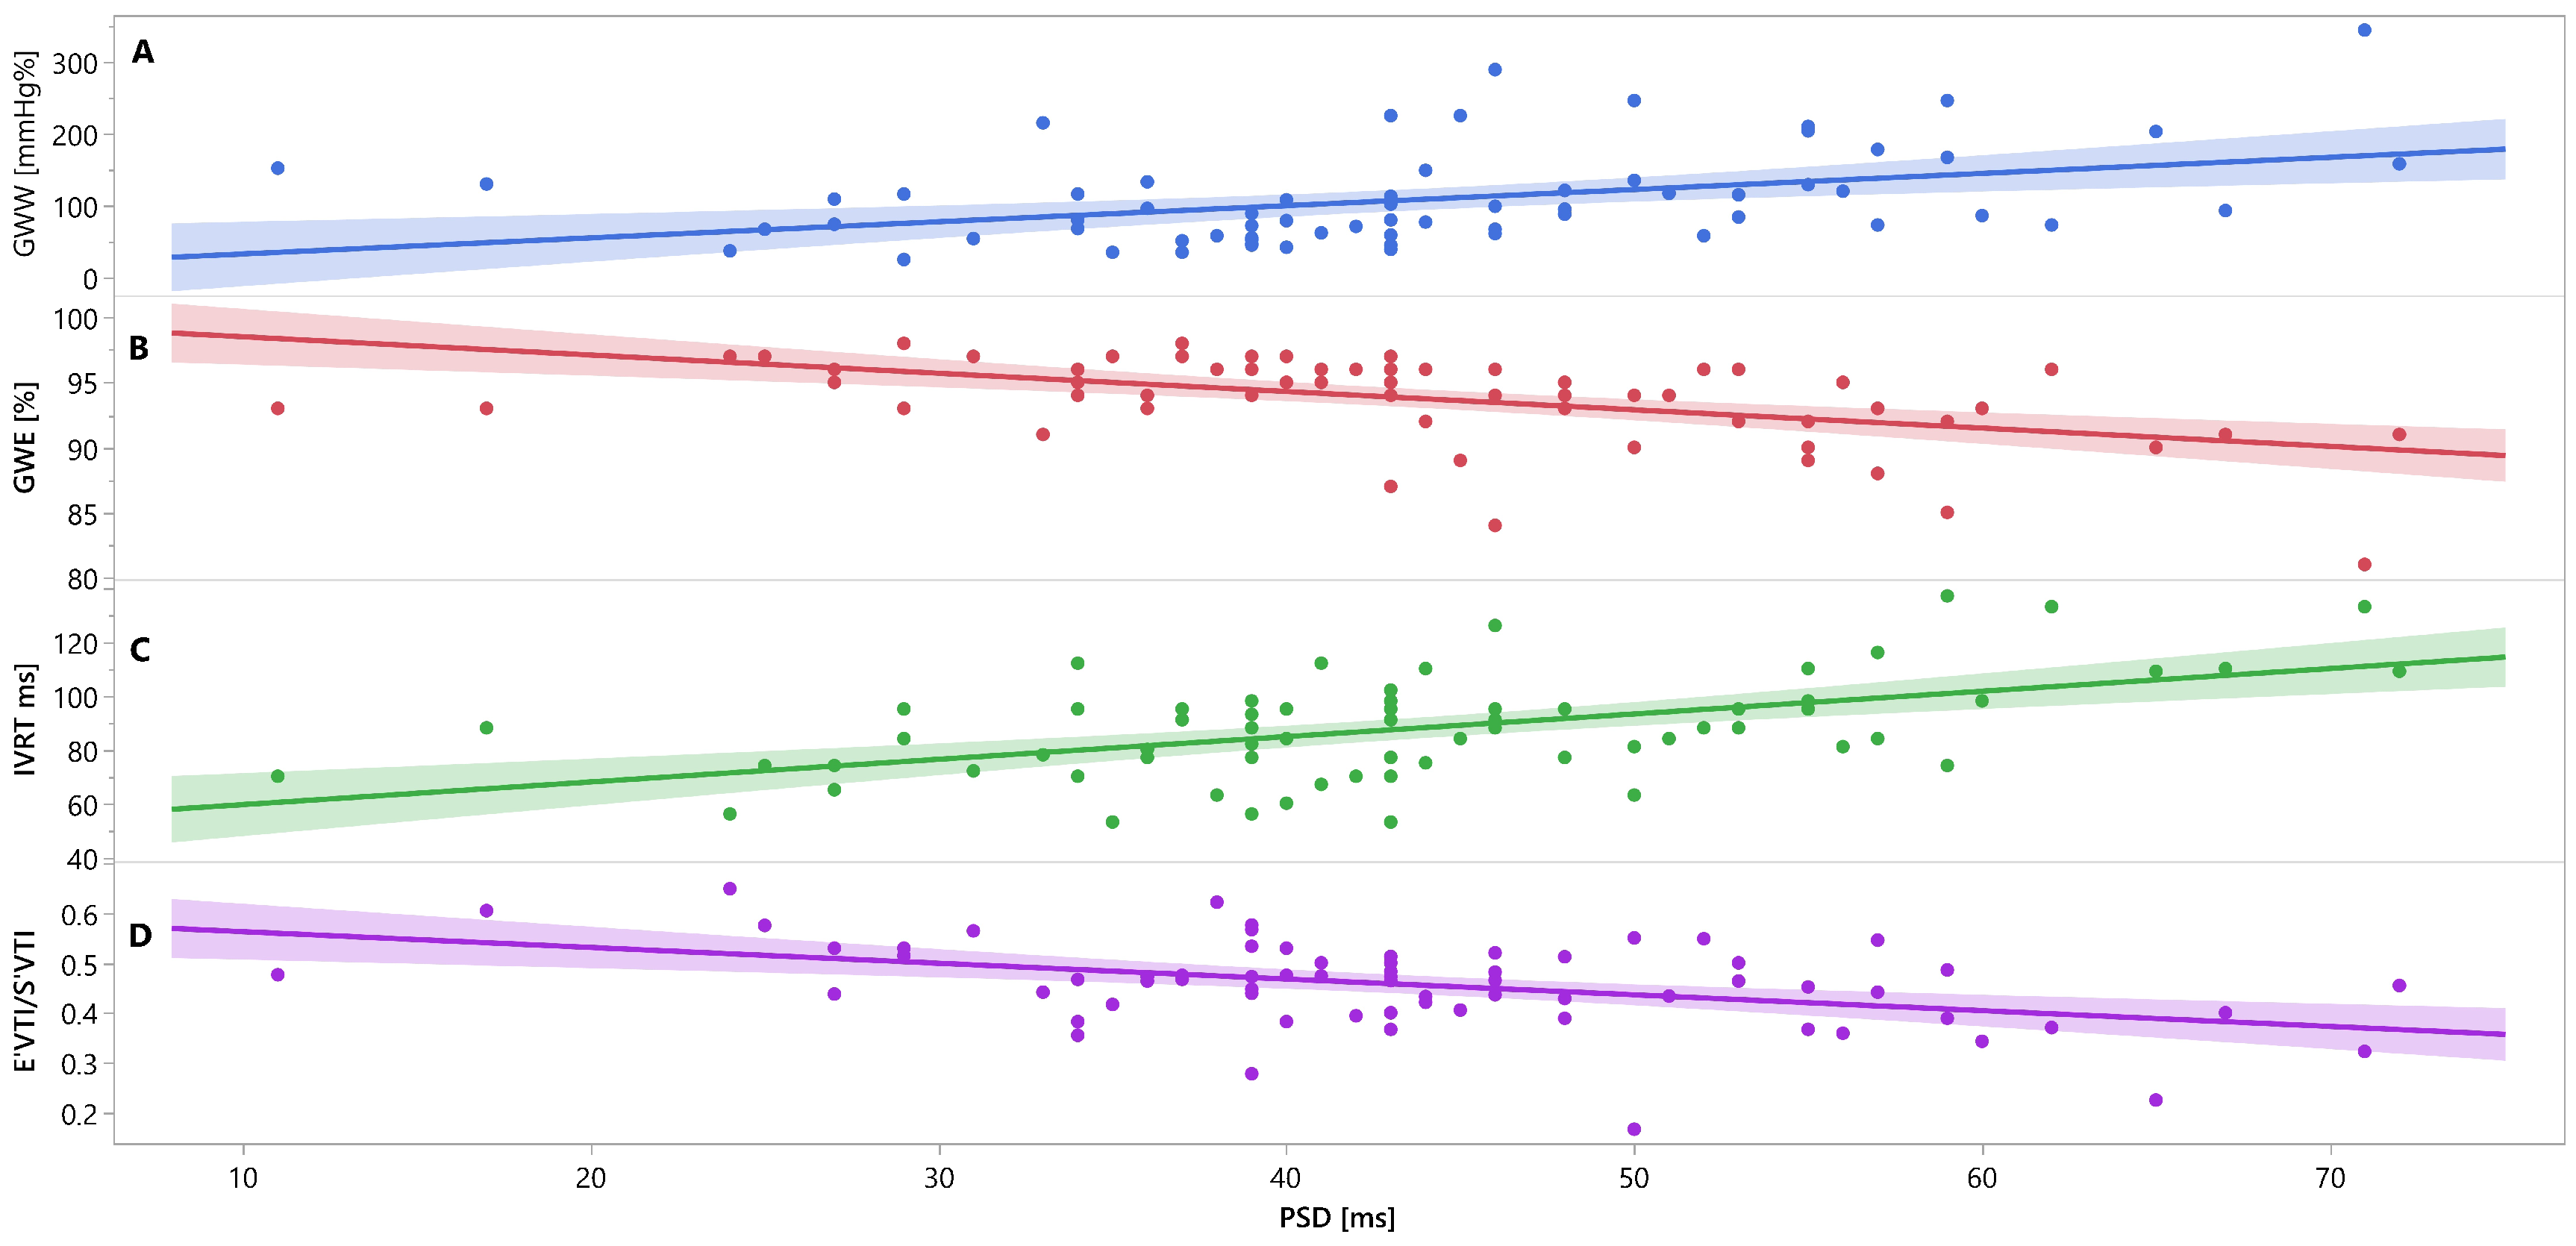

Mutual associations between PSD, GWW, GWE, IVRT and E′VTI/S′VTI are additionally shown in Figure 3, Figure 4 and Figure 5 as linear regressions.

Figure 3.

Linear regression lines for associations between PSD and GWW (panel A, line and points in blue), GWE (panel B, line and points in red), IVRT (panel C, line and points in green), and E′VTI/S′VTI (panel D, line and points in purplein healthy people. Abbreviations: E′VTI/S′VTI—systolic–diastolic coupling, GWW—global wasted work, GWE—global work efficiency, IVRT—isovolumetric relaxation time, PSD—peak systolic dispersion.